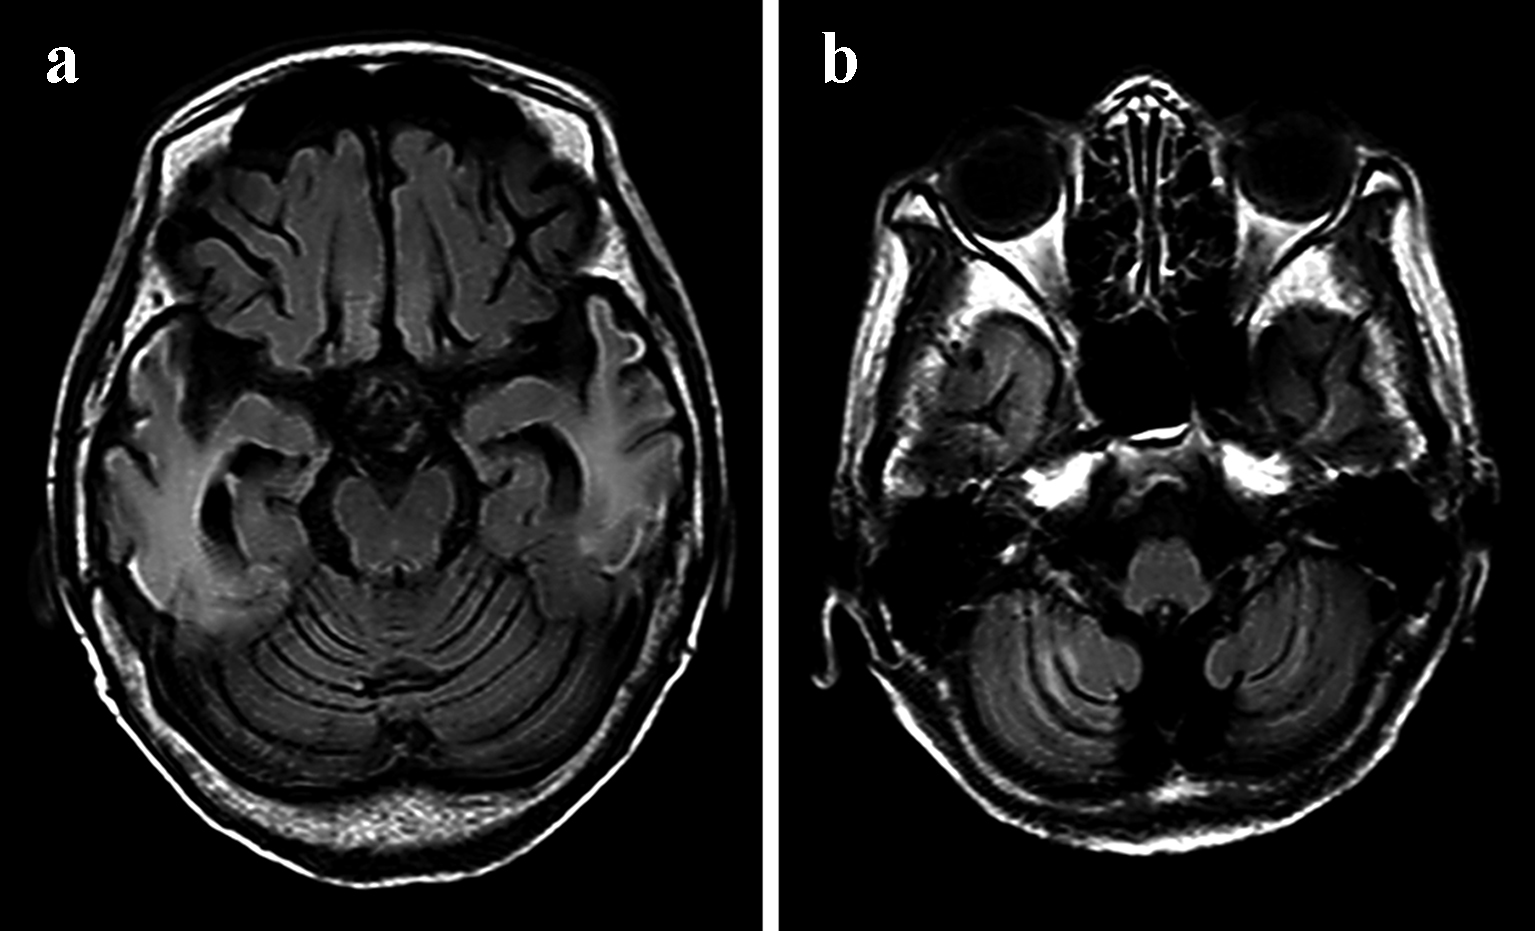

The patient previously worked as a nurse at a hospital between the ages of 18 and 25 years. At age 25, she married and quit her job to become a full-time housewife. She gave birth to a daughter at age 26 (her daughter’s current age is 43) and a son at age 28 (her son’s current age is 41). Her children are both unmarried and have no children of their own. At age 41, she began treatment for diabetes. At age 50, she began using a hearing aid. At age 67 (in May 2014), she was admitted to another hospital for a cerebral infarction (left temporal lobe; Fig. 1a, b). No evident paralyses of the limbs were noted, but the patient did exhibit a disturbance of consciousness. After admission, the patient experienced convulsive seizures. In October 2014, the patient was admitted to the same hospital for the same symptoms and received treatment for a cerebral infarction (right temporal lobe; Fig. 2a, b). In June 2015, the patient was discharged, and since that time, her impairment in terms of regarding ADL and her cognitive dysfunction have progressed rapidly. The patient’s mother had a loss of hearing, used a hearing aid, and lived to 96 years of age. The patient has seven siblings and is the fourth-born child. Her third-born sister died of kidney failure at age 19. Her other siblings are still alive, and the eldest sister is 83 years of age and is independent in terms of ADL.

![]() Click for large image | Figure 1. MRI examinations from May 2014 showing the migratory lesions of mitochondrial encephalomyopathy, lactic acidosis, and stroke-like episodes. Cortical DWI (a) and FLAIR (b) sequences revealed hyperintensity in the left temporal lobe. |